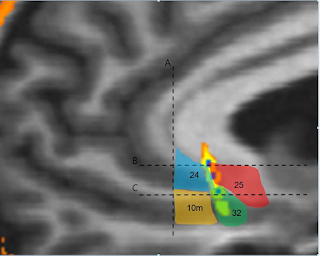

T1 + contrast MRI scan shows a large olfactory groove meningioma affecting the medial orbitofrontal cortex. Image source: Radiopedia.